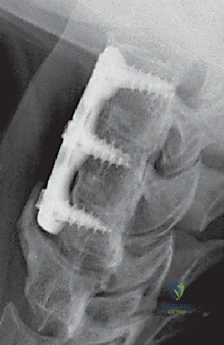

الخطوة 7: التثبيت المعدني (Instrumentation)

لضمان الاستقرار الفوري ومنع حركة الطعم العظمي حتى يكتمل الالتحام (والذي يستغرق أشهراً)، يقوم الدكتور هطيف بتثبيت شريحة معدنية صغيرة من التيتانيوم على الجزء الأمامي من الفقرتين باستخدام براغي دقيقة.

الخطوة 8: الإغلاق التجميلي